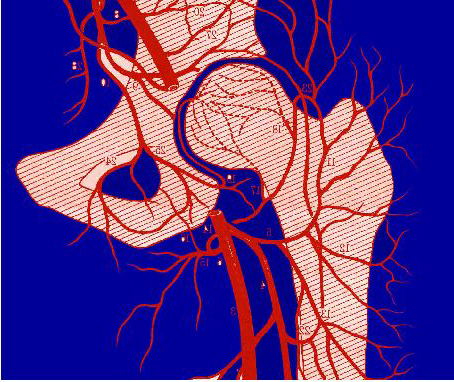

成年人早期股骨头坏死

股骨头坏死(nosteonecrosis of femoral head)是由各种病因引起股骨头血液供应破坏而引起软骨下骨变性、坏死,造成股骨头塌陷,最终导致髋关节退行性破坏。ESWT 可以治疗成年人早期股骨头缺血坏死,延缓股骨头坏死的进展,其疗效与钻孔减压类似。